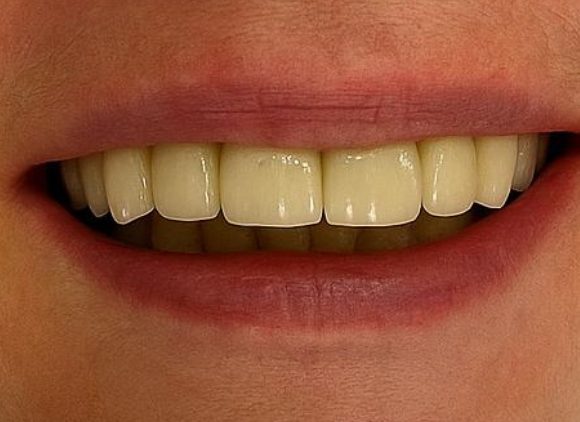

Before

After